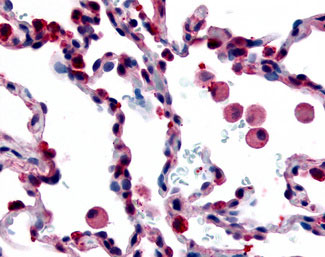

Anti-FFAR2 / GPR43 antibody IHC of human Pancreas, Carcinoma.

Anti-GPR43 antibody APR15965G IHC of human lung, alveolar macrophages. |